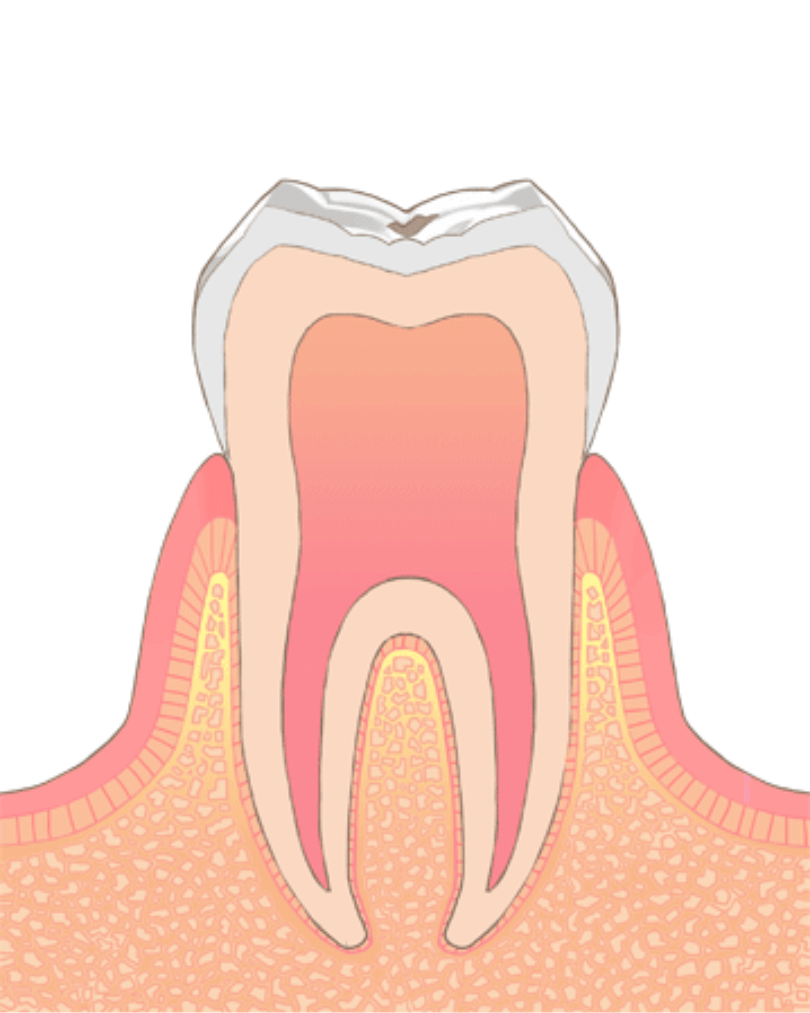

虫歯の進行段階と治療法

小さい虫歯(C0~1:歯の表面の白濁~エナメル質内)

虫歯が小さいものであれば、虫歯の部分のみを削り取り、「コンポジットレジン治療」により1回で治療することが可能です。

また、エナメル質(歯の一番外側の層)表層のみにとどまった非常に小さい虫歯であれば、治療をせずに経過観察をすることもあります。

症状の目安

冷水や甘みにしみる程度

治療

経過観察、レジン治療

やや大きい虫歯(C2:象牙質まで進行)

虫歯が大きくなり、象牙質(歯の内側の層)にまで進行してしまっている場合には、コンポジットレジン治療に加え、歯を削った部分の歯型を取ってつめ物をする「インレー(アンレー)治療」も選択肢として出てます。

また、虫歯の進行具合に応じて、虫歯を除去後、神経を保護する処置をして、経過観察する事もあります。

治療には2回~3回程度の通院が必要な事が多いです。

しみる、軽度の痛み

レジン、インレー治療

大きい虫歯 (C3:歯髄まで進行)

虫歯が歯の部分全体に及んでいる場合には、歯、全体を覆うさし歯「クラウン治療」が必要になります。

さらに、虫歯が神経にまで達している場合には、歯の神経を取り除き、根管をきれいにするための根管治療が必要になってきます。

根管治療は、状態が良ければ2~3回で完了できますが、状態によってはそれ以上、数か月に及ぶこともあります。

激しいズキズキ痛み・夜間痛

根管治療+さし歯

抜歯が必要なほど大きな虫歯 (C4:残根状態)

虫歯が大きくなり、歯根部分にまで及んでしまっている場合には、抜歯が必要となってしまいます。

抜歯をした場合には、抜いた部分を修復するための治療を行います。

欠損修復には、インプラント、ブリッジ、入れ歯などがあり、それぞれにメリット・デメリットがあります。

歯が崩壊

抜歯+インプラント、ブリッジ、入れ歯